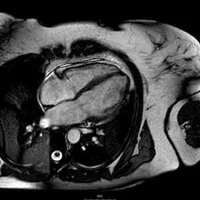

Qual exame está representado em cada imagem? Qual deles é o melhor para avaliar grau de estenose?

1.Angiotomografia de tórax / 2. Angiotomografia coronariana / 3. Ressonância Magnética / 4. Cateterismo cardíaco. | Cateterismo cardíaco

1.Angiografia /2. Angiotomografia coronariana / 3. Ressonância Magnética / 4. Cateterismo cardíaco. | Cateterismo cardíaco

1.Angiotomografia de tórax / 2. Angiotomografia coronariana / 3. Ressonância Magnética / 4. Cateterismo cardíaco. | Ressonância Magnética